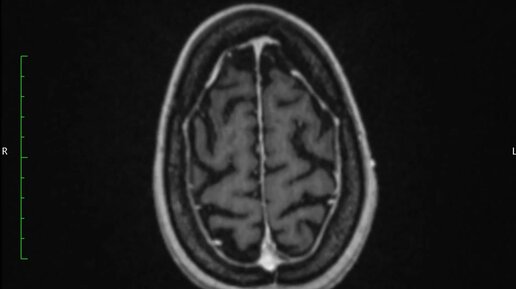

Что покажут снимки МРТ головного мозга